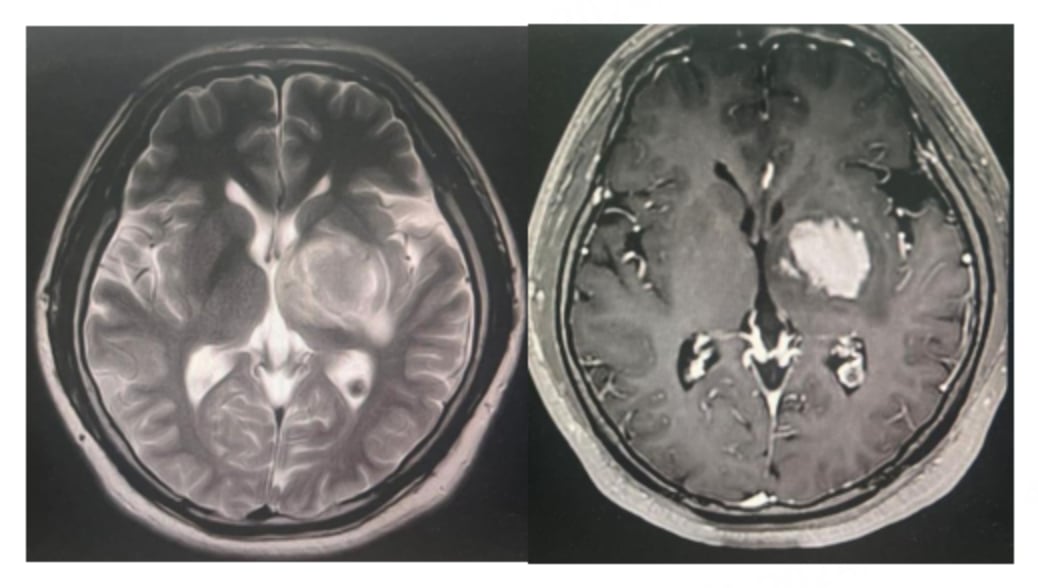

由于患者无法再次进行放疗,医疗团队决定采用以替尼泊苷为核心的联合化疗方案。具体用药包括:利妥昔单抗、替尼泊苷、异环磷酰胺、顺铂和地塞米松。经过3个疗程的治疗后,影像学评估显示患者达到了部分缓解(PR),颅内病灶明显缩小,病情得到有效控制。

面对棘手的病情,医生同样采用了基于替尼泊苷的联合化疗方案。在第一个疗程后,患者出现了粒细胞缺乏伴发热的副作用,医生及时将后续化疗剂量减少了25%。经过调整后的3个疗程治疗,患者的症状显著改善,复查影像显示病灶缩小,同样达到了部分缓解(PR)。